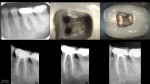

In today regarding this tooth I treated in 2005.

Stepped access, two step crown repair with amalgam internal core with HF etched, silanated, opaqued and resin veneer.

Shapes were ProFile S29 #5/.06 mesials, #6/.06 distals…large for that time but I was trying it out to see if it made any difference.  Normal shapes at that time would probably have been a #3 or #4 mesials, #4 or #5 distals.*

10 year followup shown.

*S29 ProFiles where "Schilder inspired" safe-ended, landed rotary NiTi with a 29% increase in diameter.  A #4 was around a 20/.06, and a #5 was around a 30/.06 and a #6 was around a 35/.06…so those were not that big of a shape.